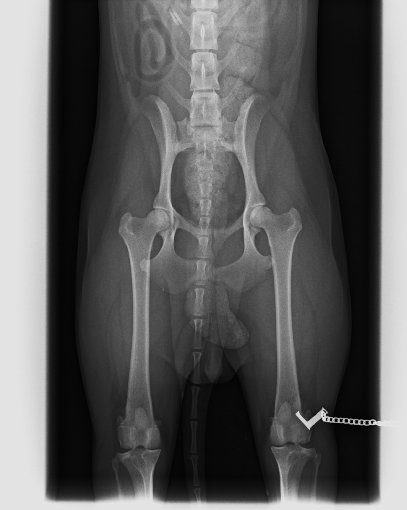

HD-A

HD-A1